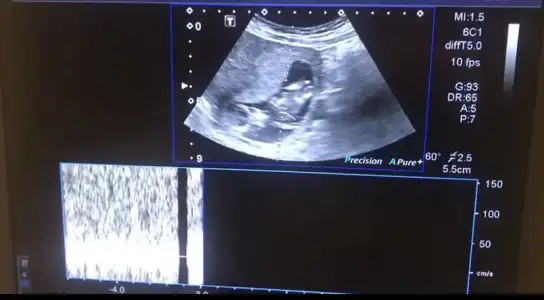

Canlarım ciğerlerimmm nolur vanada yorum yapın çatlicam. Doktor yorum yapmadı. 23. Haftamdayım. Sizce cinsiyet neeeeeee